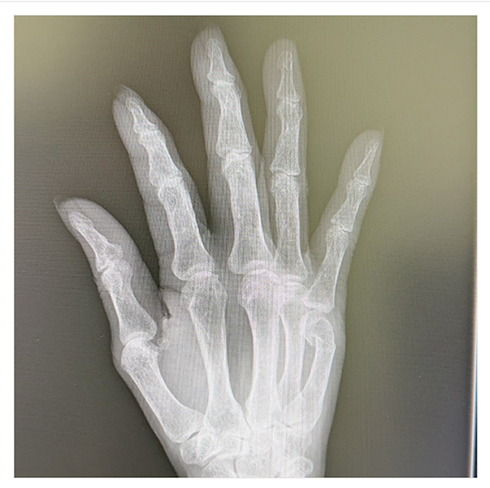

折れた骨が内側に入り込んでしまったレントゲンや痛々しいギプスの写真とともに経過を報告していた小柳さんですが、年が明けた2024年1月10日には「経過観察の結果です 結論から言いますと最悪の結果でした」とショックを隠せない様子で投稿。

小柳さんによると、「折れた骨が 又 折れてて内側に倒れていました」とかなり状態が悪化していたとのこと。しかも、その状態で骨癒合し始めていたため、麻酔を受けて人工的に患部を再度骨折させてから正しい位置に戻すという処置に臨んだそうです。